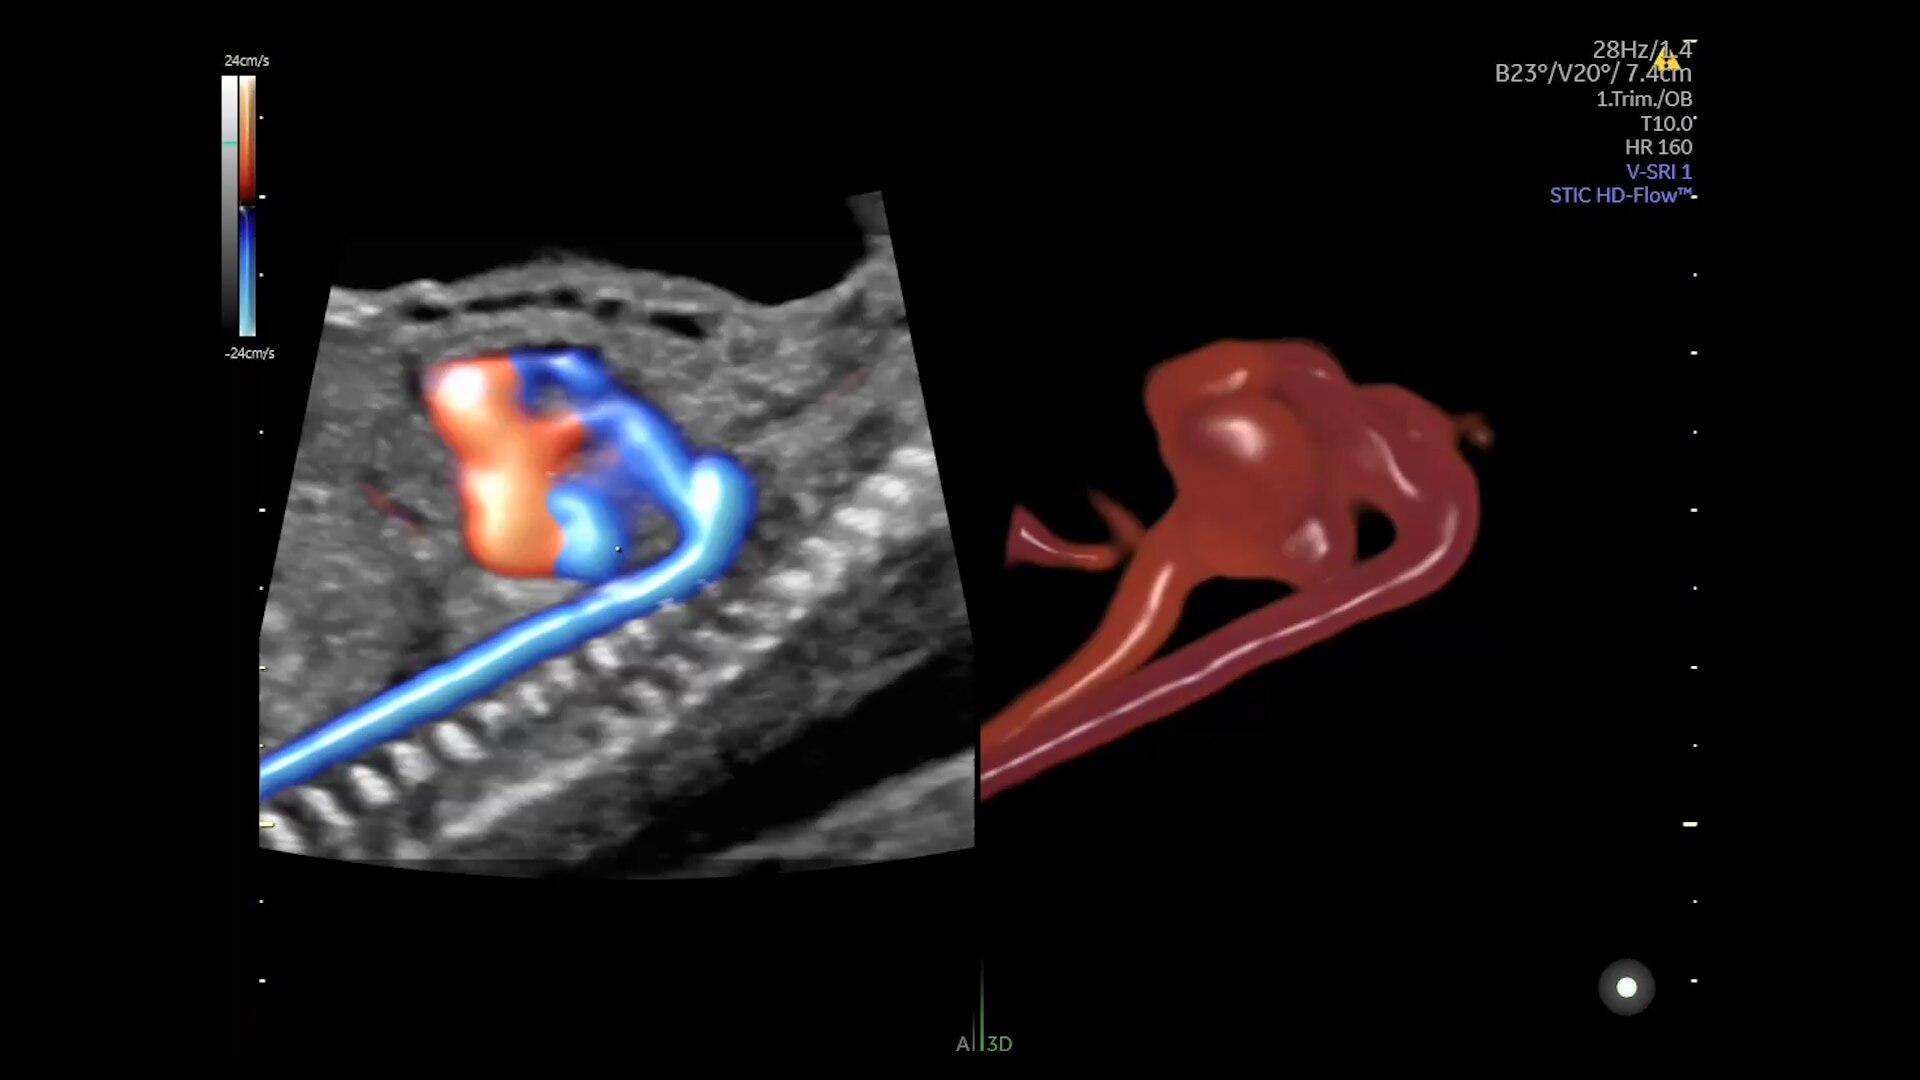

Enhanced Volume Imaging

Deliver next generation 3D/4D & Color images with HDlive Studio+

Unique Probe Technology

Obtain high resolution images with advanced probe technology - eM6C, RIC6-12, and RM7C